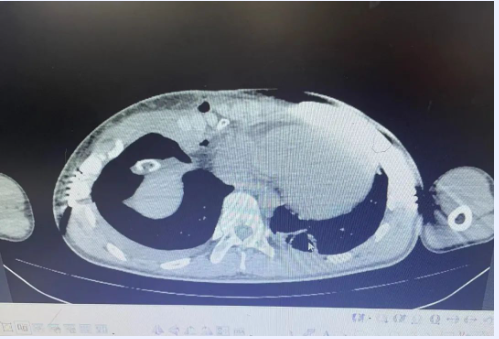

小冯随着年龄的增长,症状愈发严重,父母焦急万分,带着小冯到我院胸心外科就诊。胸心外科团队通过完善相关检查,发现小冯胸廓向内凹陷成漏斗状,且凹陷最深处偏向右侧,漏斗指数FI>0.3,评估为重度畸形。

通常漏斗胸最佳手术时间是6-12岁,而小冯已经15岁,骨骼架构基本定型,骨骼柔韧度较差,畸形严重且特殊,矫形难度剧增。团队考虑到对该患者采用目前我院较成熟的“NUSS(漏斗胸微创矫正术)”,此手术是漏斗胸最常采用的手术方式,但需进入胸腔,小冯胸腔内手术操作空间小,有损伤心脏和大血管的风险,主任李祥带领团队多次深入探讨和研究,为小冯制定了充分详细的个性化手术方案,征得家属同意后,决定对小冯实施微创“wang”手术,此手术不需进入胸腔,完全在胸腔外操作,大大降低了手术风险又可以达到矫形效果。

经过充分术前准备,主任李祥带领团队与麻醉团队的密切配合、紧密协作下,术程顺利,成功为小冯实施了“漏斗胸矫正术”。术后小冯胸壁凹陷消失,胸廓恢复正常形态,患者及家属对手术效果非常满意。“悬了15年的心终于放下了”小冯母亲激动的说道。